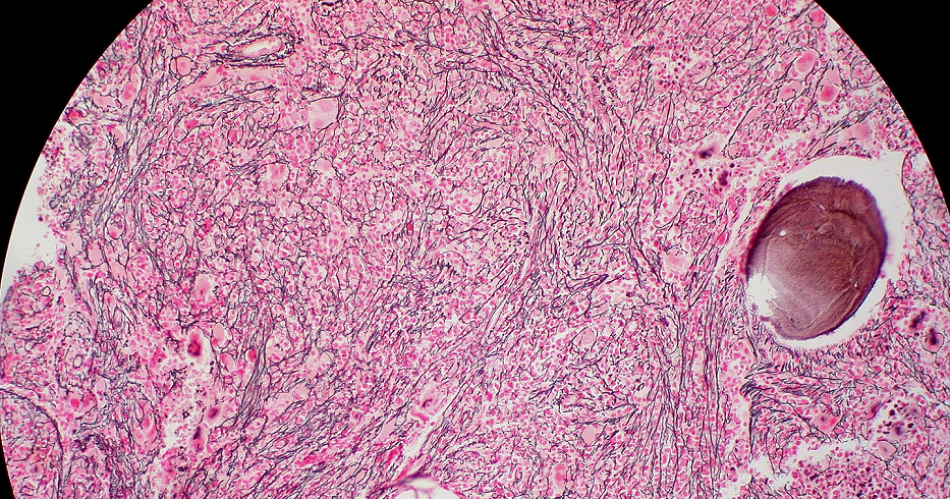

Un ejemplo de estas enfermedades es la mielofibrosis, una enfermedad poco frecuente de la medula ósea, caracterizada en etapas iniciales por la producción descontrolada de glóbulos rojos, glóbulos blancos y plaquetas. Con el tiempo el ambiente medular se va reemplazando por tejido fibroso impidiendo el correcto funcionamiento de las células madre productoras de las células de la sangre y así pudiendo producir anemia, predisposición a infecciones y sangrados. Los pacientes afectados, en general son personas mayores de 50 años. Actualmente, no se conoce fehacientemente la incidencia ni la prevalencia de la mielofibrosis en la Argentina. En general, los datos de otros países muestran que la enfermedad es poco frecuente.

En etapas tempranas los pacientes pueden tener solo alteraciones leves de laboratorio y si la enfermedad avanza suelen presentar síntomas como fiebre, pérdida de peso significativa, sudoración nocturna, anemia, cansancio extremo y, sobre todo, un agrandamiento considerable del bazo. Este aumento del tamaño del bazo se produce por el desplazamiento de células madre de la médula ósea a la sangre, desde donde colonizan órganos a distancia, fundamentalmente, el bazo y el hígado. Generalmente inicia en forma asintomática por lo que muchas veces se diagnostica luego de que la persona presenta valores anormales de laboratorio en un chequeo habitual de salud y puede evolucionar de forma muy lenta sin necesidad de tratamiento por muchos años.

Los pacientes llegan al hematólogo derivados por el médico clínico, quien observa algún indicador alterado en un análisis de rutina o el aumento del tamaño del bazo. El diagnóstico es clínico y se confirma mediante estudios genéticos y una punción de la médula ósea. Es de suma importancia un diagnóstico adecuado, en que se reconozca y piense en esta enfermedad. A veces, puede pasar que el paciente tenga una trombosis en los vasos abdominales o problemas de hipertensión portal y hemorragias digestivas como forma de presentación y lo que no se sabe es que en realidad tiene mielofibrosis.